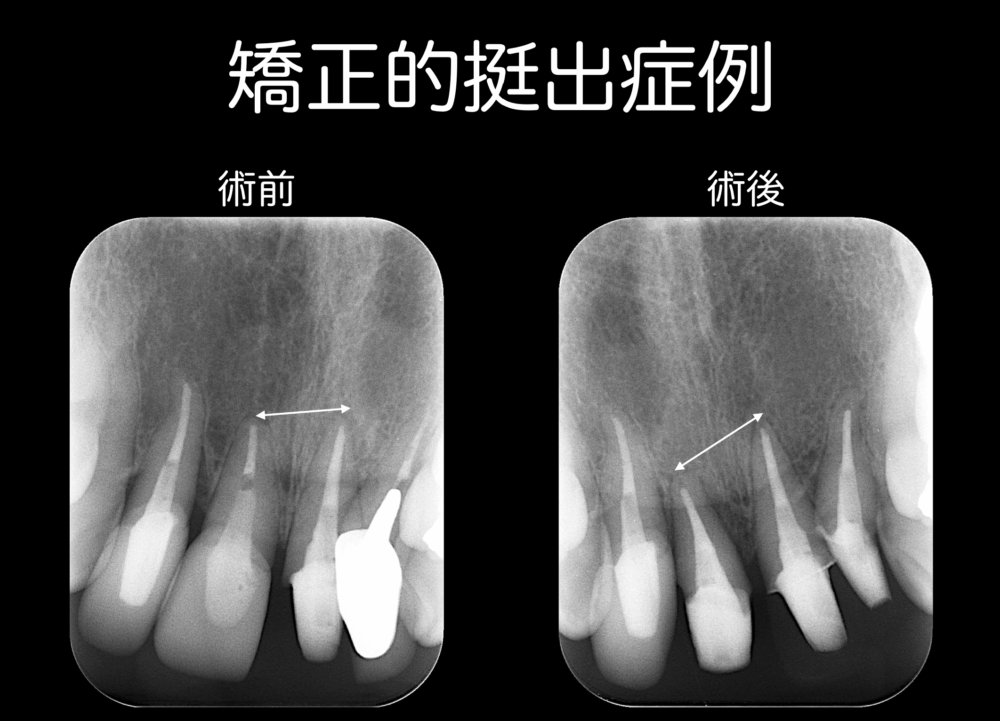

左の写真は、歯が歯肉より下にある歯で、生物学的幅径を確保した方が理想的です。右の写真の矢印の部位は、挺出により歯が歯肉と同等になっているところで、生物学的幅径を確保できています。理想は、歯肉と歯が同じ位置にあることです。よって、この写真の症例は、まだ生物学的幅径が全体で確保できていない状況です。

右上のレントゲンの矢印でわかるように、

術前のレントゲンの根尖の位置と術後の根尖の位置がずいぶん変わっています。